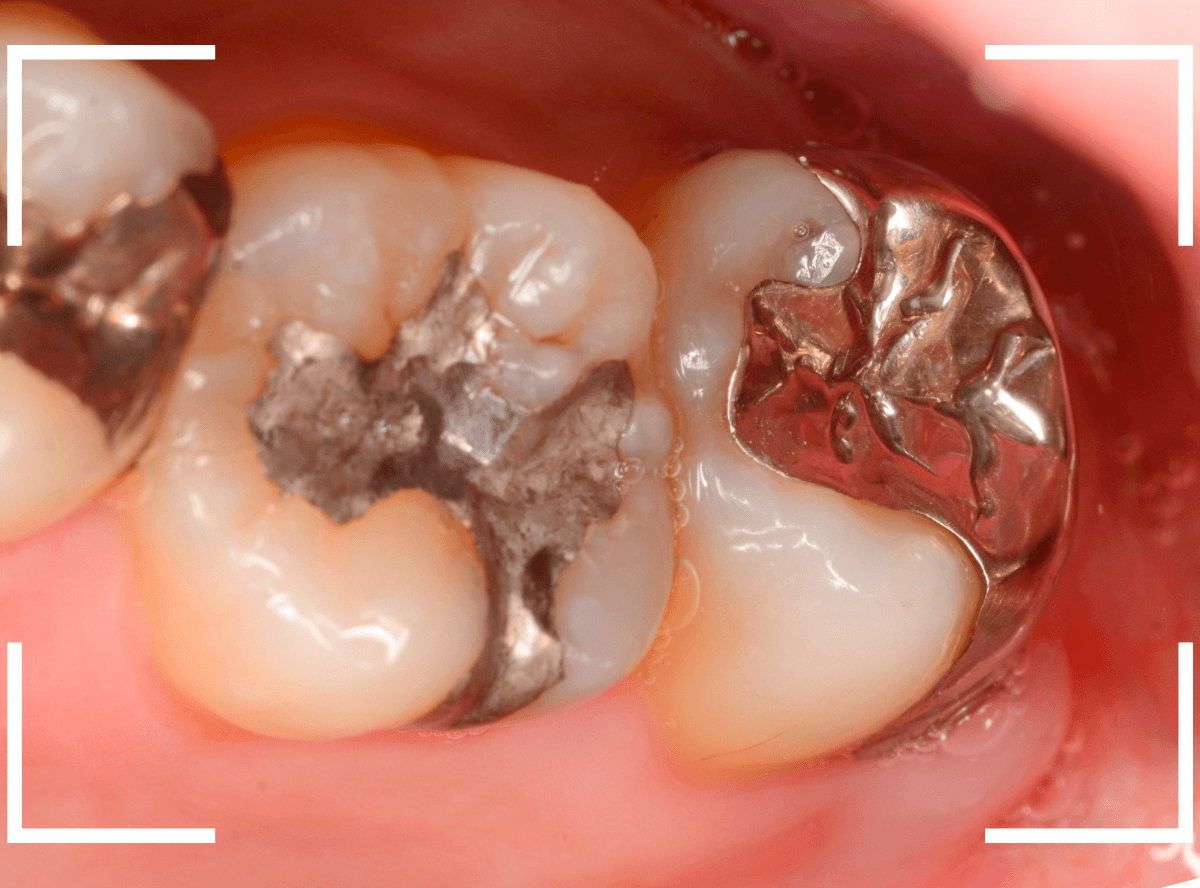

Case.1 隣り合った2本が大きな虫歯

「下の歯の奥から2番目の歯が痛む」という患者さんです。

お口の中を拝見すると、何だか1番奥の歯も怪しそうなので、歯を叩いて症状を確認してみます(打診)。

やっぱり奥から2番目の歯が痛むけど、1番奥の歯も少し痛むそうです。

レントゲン写真で確認してみました。

やはりどちらの歯も大きな虫歯でした。

2番目の歯が痛みの原因なのかもしれませんが、1番奥の歯の可能性も大いにあります。

両方の歯が原因かもしれません。

いずれにせよ、両歯とも痛みを神経に近い虫歯ですので、神経が炎症を起こして本格的な痛みになる前に治療をして神経の治療(抜髄)にならない可能性を少しでも上げたいところです。

通常であれば、初診時に大きな虫歯治療を2本行う時間的な余裕もありませんので、患者さんに事情を説明して後日治療になるのですが、今回は、予約時間よりも余裕をもって早めに来院していただいた患者さんだったので、何とか当日治療まで進める事ができました♪

まずは、麻酔をしてつめ物を慎重に外してみます。

両歯とも、色々嫌な予感のする所見です。

虫歯を可視化する、「う蝕検知液」で染め出ししてみます。

赤く染まっている場所が虫歯で、濃く染まっているところほど、虫歯は深いです。

手前の歯は一部神経が見えそうなところまで虫歯が来ていました(●部)。

患者さんのおっしゃるように、この歯が痛みの原因だったのかもしれません。

後ろの歯も、幸い神経は見えていませんが、かなり広く深い虫歯で心配な状況です。

急いで、神経を保護する薬を入れた後に、セメントで蓋をして経過観察します。

ほとんどの方はこれで何とかなりますが、痛みが出てしまい、神経の治療が必要になる方もいます。

神経の治療をすると歯の寿命は短くなってしまうので、できるだけ避けたいところです。

慎重に経過観察します。